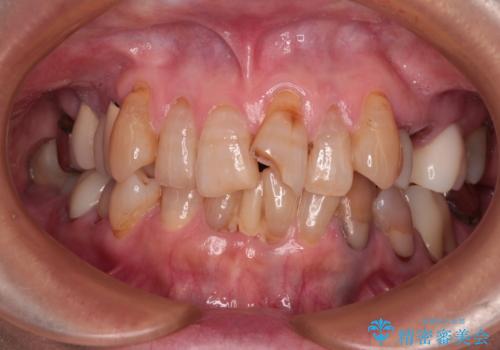

捻れて前に出ている前歯 ワイヤー装置での非抜歯矯正

受け口と八重歯を改善 インビザライン矯正治療

長年気になっていた前歯 矯正治療と補綴治療による審美歯科治療